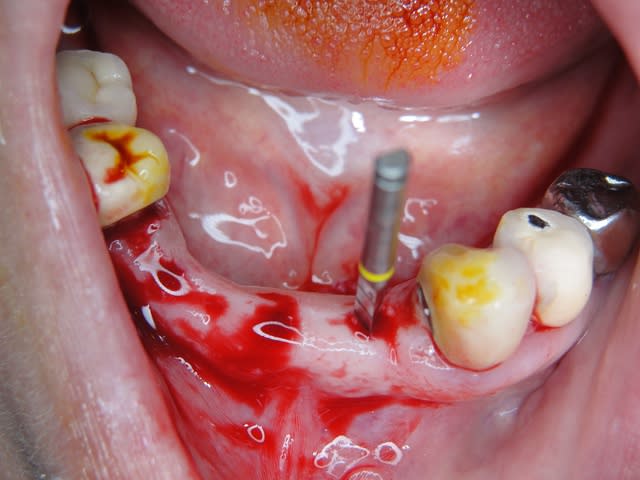

Exp dans ce cas 4,5/10mm en 36 dans un site d'extraction récent placé en 12mm soit deux millimètres plus profondément j'ai scellé un prep cap angulé 5 degrés niveau 1/0 dont la limite s'arrête à la rainure de la tête carrée, pour 37 3,5/10mm placé en 10mm j'ai utilisé un prep cap 2/2mm. On prend vite l'habitude moi j'utilise que 2 modèles en zircone et 3 en titane..

Maintenant concernant la demande de scans : je poste ce cas, une patiente vient me voir avec son scan car elle a consulté d'autres "spécialistes" et on lui refuse la pose d'implant secteur 4 où alors avec greffe préalable..Ca se discute..pas de temps à perdre je sais faire autrement..

Avec la chir trans gingivale technique MIMI ( Oui..un post sur la technique bientôt ..) j'ai pu placer deux 3,5/8mm..aurai je eu le meme résultat avec un lambeau..j'en doute..Les couronnes sont en titane. Recul clinique 2 ans ras. Simple efficace rapide moins onéreux satisfaisant pour le praticien et la patiente..